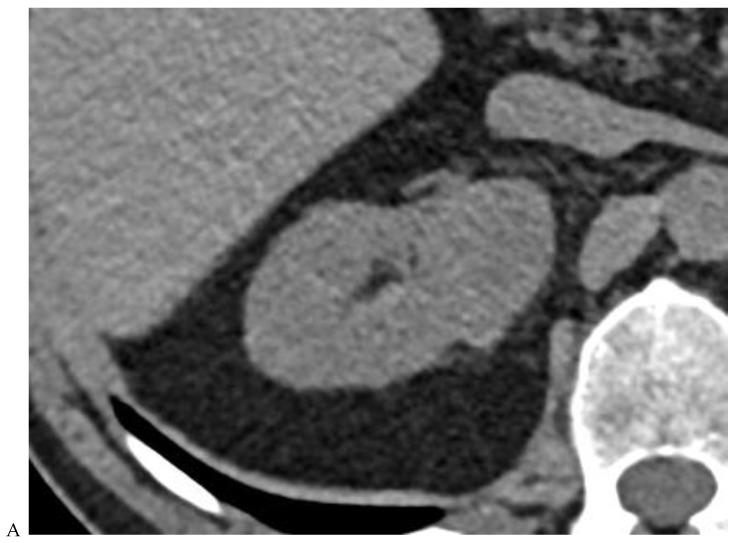

This review highlights recent advances in renal cell carcinoma (RCC) imaging. It begins with dual-energy computed tomography (DECT), which has demonstrated a high diagnostic accuracy in the evaluation of renal masses. Several studies have suggested the potential benefits of iodine quantification, particularly for distinguishing low-attenuation, true enhancing solid masses from hyperdense cysts. By determining whether or not a renal mass is present, DECT could avoid the need for additional imaging studies, thereby reducing healthcare costs. DECT can also provide virtual unenhanced images, helping to reduce radiation exposure. The review then provides an update focusing on the advantages of multiparametric magnetic resonance (MR) imaging performance in the histological subtyping of RCC and in the differentiation of benign from malignant renal masses. A proposed standardized stepwise reading of images helps to identify clear cell RCC and papillary RCC with a high accuracy. Contrast-enhanced ultrasound may represent a promising diagnostic tool for the characterization of solid and cystic renal masses. Several combined pharmaceutical imaging strategies using both sestamibi and PSMA offer new opportunities in the diagnosis and staging of RCC, but their role in risk stratification needs to be evaluated. Although radiomics and tumor texture analysis are hampered by poor reproducibility and need standardization, they show promise in identifying new biomarkers for predicting tumor histology, clinical outcomes, overall survival, and the response to therapy. They have a wide range of potential applications but are still in the research phase. Artificial intelligence (AI) has shown encouraging results in tumor classification, grade, and prognosis. It is expected to play an important role in assessing the treatment response and advancing personalized medicine. The review then focuses on recently updated algorithms and guidelines. The Bosniak classification version 2019 incorporates MRI, precisely defines previously vague imaging terms, and allows a greater proportion of masses to be placed in lower-risk classes. Recent studies have reported an improved specificity of the higher-risk categories and better inter-reader agreement. The clear cell likelihood score, which adds standardization to the characterization of solid renal masses on MRI, has been validated in recent studies with high interobserver agreement. Finally, the review discusses the key imaging implications of the 2017 AUA guidelines for renal masses and localized renal cancer.

本综述重点介绍了肾细胞癌(RCC)成像的最新进展。首先是双能计算机断层扫描(DECT),它在评估肾肿块方面已显示出较高的诊断准确性。多项研究表明碘定量具有潜在益处,特别是在区分低衰减、真正强化的实性肿块与高密度囊肿方面。通过确定是否存在肾肿块,DECT可以避免进行额外的影像学检查,从而降低医疗成本。DECT还可以提供虚拟平扫图像,有助于减少辐射暴露。该综述接着介绍了最新进展,重点是多参数磁共振(MR)成像在RCC组织学亚型分类以及肾良性与恶性肿块鉴别方面的优势。一种提议的标准化图像逐步解读方法有助于高精度地识别透明细胞RCC和乳头状RCC。对比增强超声可能是一种用于实性和囊性肾肿块特征化的有前景的诊断工具。几种同时使用锝[99mTc]甲氧基异丁基异腈(sestamibi)和前列腺特异性膜抗原(PSMA)的联合药物成像策略为RCC的诊断和分期提供了新机会,但其在风险分层中的作用有待评估。尽管放射组学和肿瘤纹理分析因可重复性差且需要标准化而受到阻碍,但它们在识别预测肿瘤组织学、临床结果、总生存期和治疗反应的新生物标志物方面显示出前景。它们有广泛的潜在应用,但仍处于研究阶段。人工智能(AI)在肿瘤分类、分级和预后方面已取得令人鼓舞的结果。预计其在评估治疗反应和推进个性化医疗方面将发挥重要作用。该综述接着重点介绍了最近更新的算法和指南。2019年版的博斯尼亚克分类纳入了MRI,精确定义了以前模糊的影像学术语,并允许将更大比例的肿块归类为低风险类别。最近的研究报告称,高风险类别的特异性有所提高,阅片者之间的一致性也更好。透明细胞可能性评分在MRI上对实性肾肿块的特征化增加了标准化,最近的研究已验证其具有较高的观察者间一致性。最后,该综述讨论了2017年美国泌尿协会(AUA)肾肿块和局限性肾癌指南的关键影像学意义。